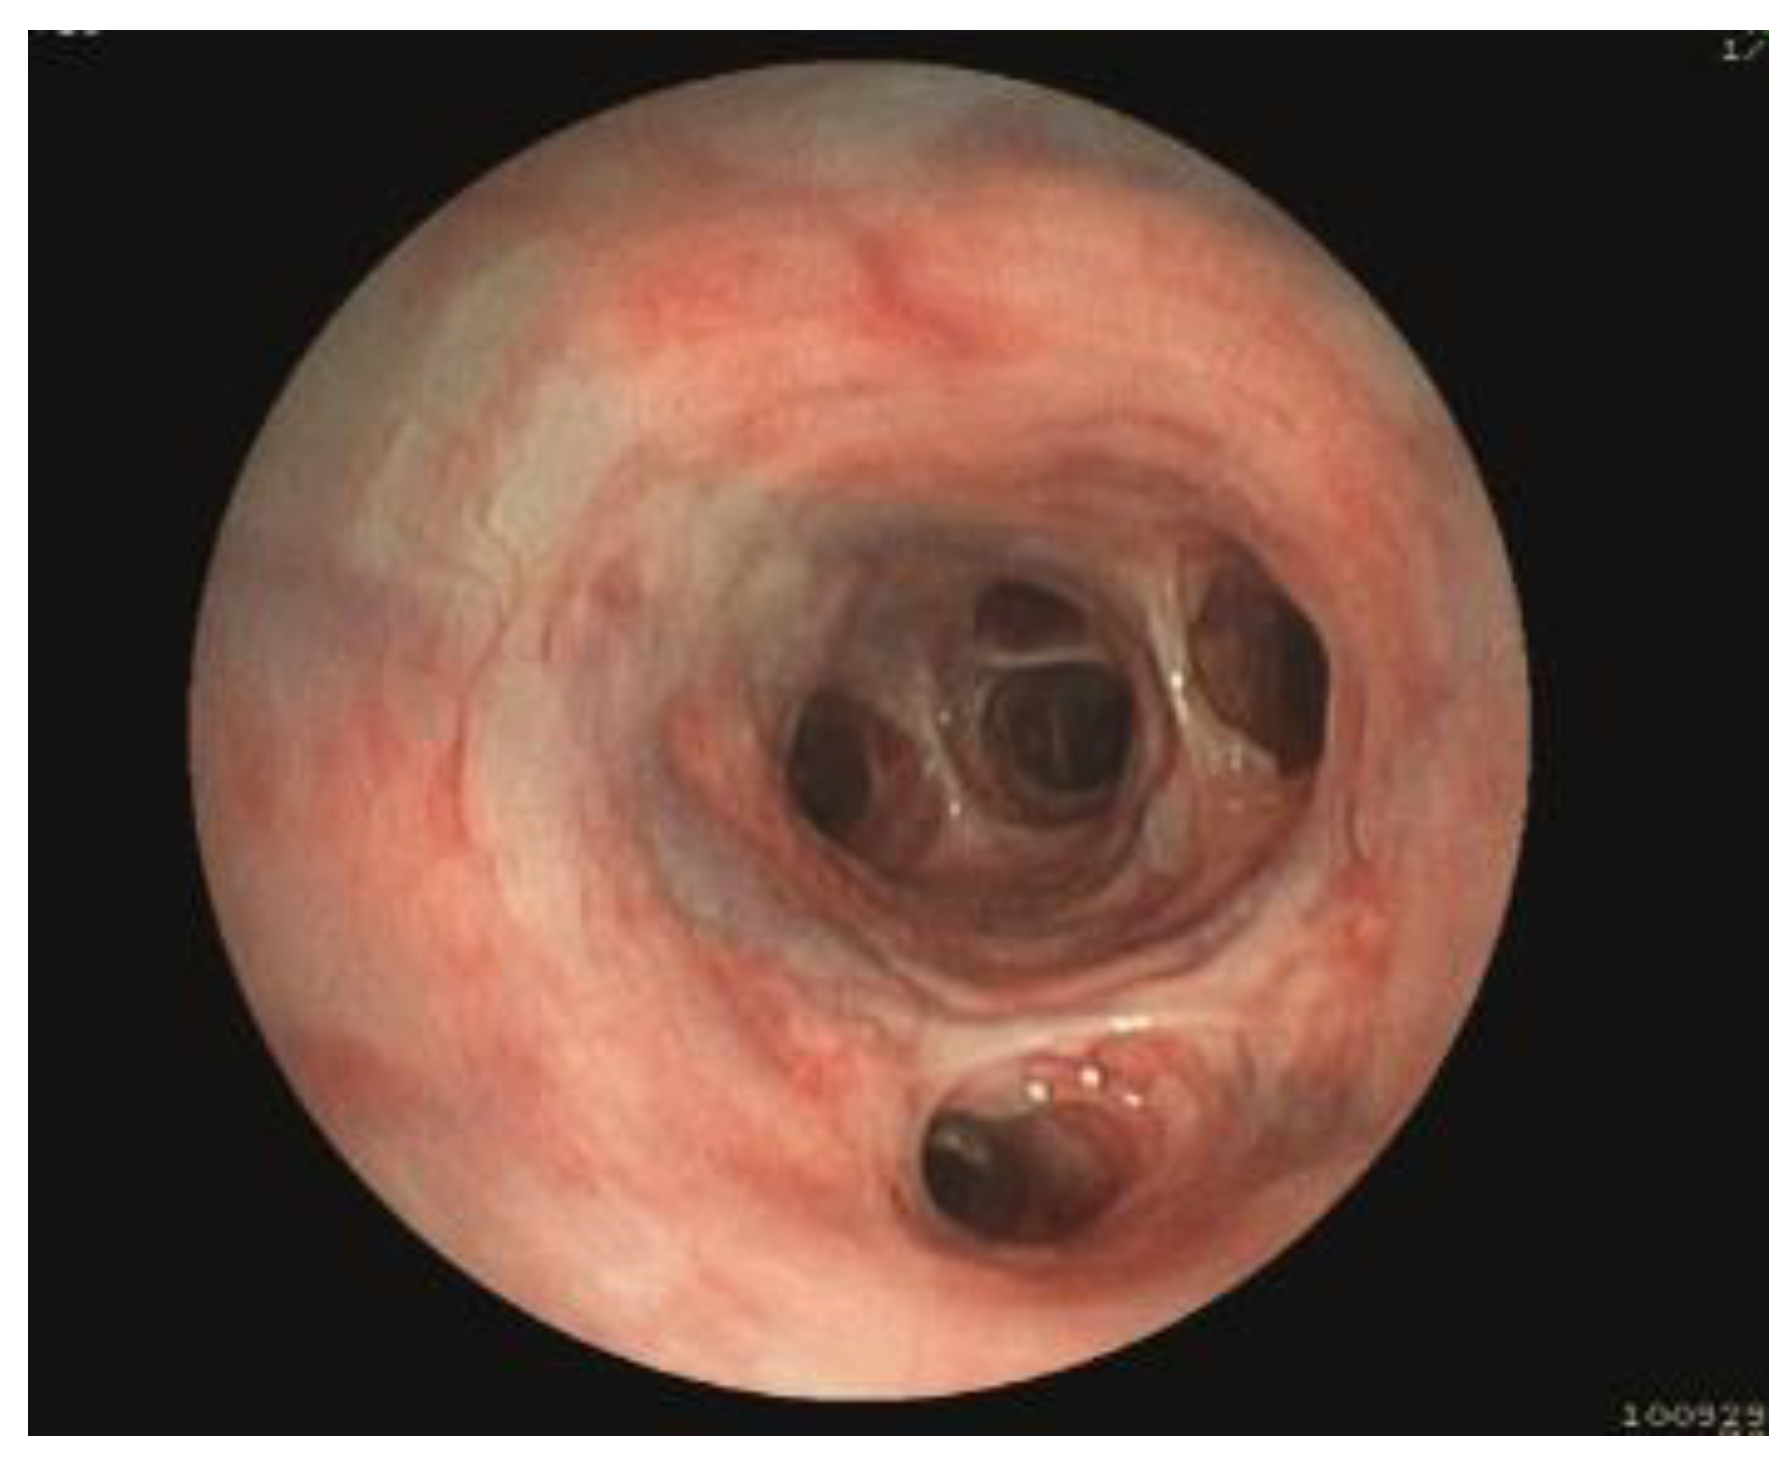

3.1.6. BALF Cytological and Microbiological Analysis

- Bottero, E.; Bellino, C.; De Lorenzi, D.; Ruggiero, P.; Tarducci, A.; D’Angelo, A.; Gianella, P. Clinical evaluation and endoscopic classification of bronchomalacia in dogs. J. Vet. Intern. Med. 2013, 27, 840–846. [Google Scholar] [CrossRef]